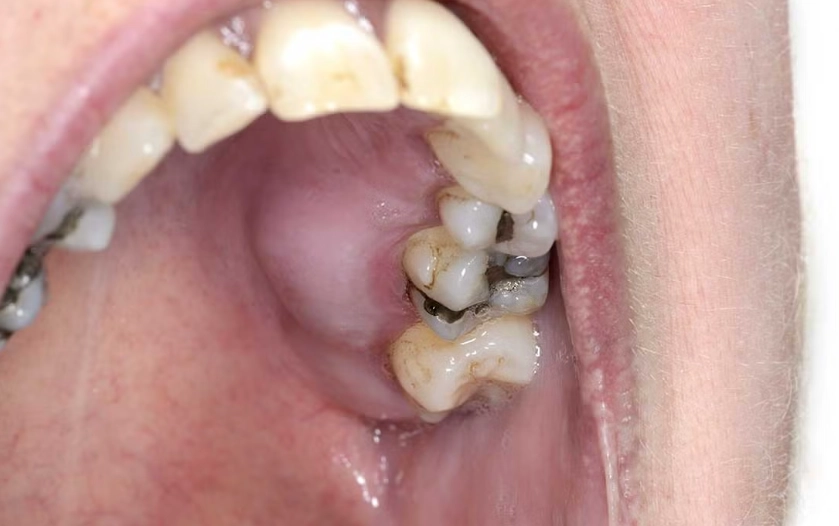

Think of it as a pus-filled pocket at the very tip of your tooth's root. It happens when bacteria invade the tooth's pulp (the soft inner part with nerves and blood vessels), usually through a deep cavity or a crack. The bacteria party at the root tip, your body sends in immune cells to fight, and the resulting battle debris forms pus. That pressure is what causes that intense, persistent ache.

Now, the common scenario: you have a bad toothache, maybe some localized gum tenderness, but no fever, no major swelling, and you feel okay otherwise. In this case, the definitive treatment is not antibiotics. It's removing the source of the infection. That means a root canal treatment or, if the tooth can't be saved, an extraction. The antibiotic prescription might wait.